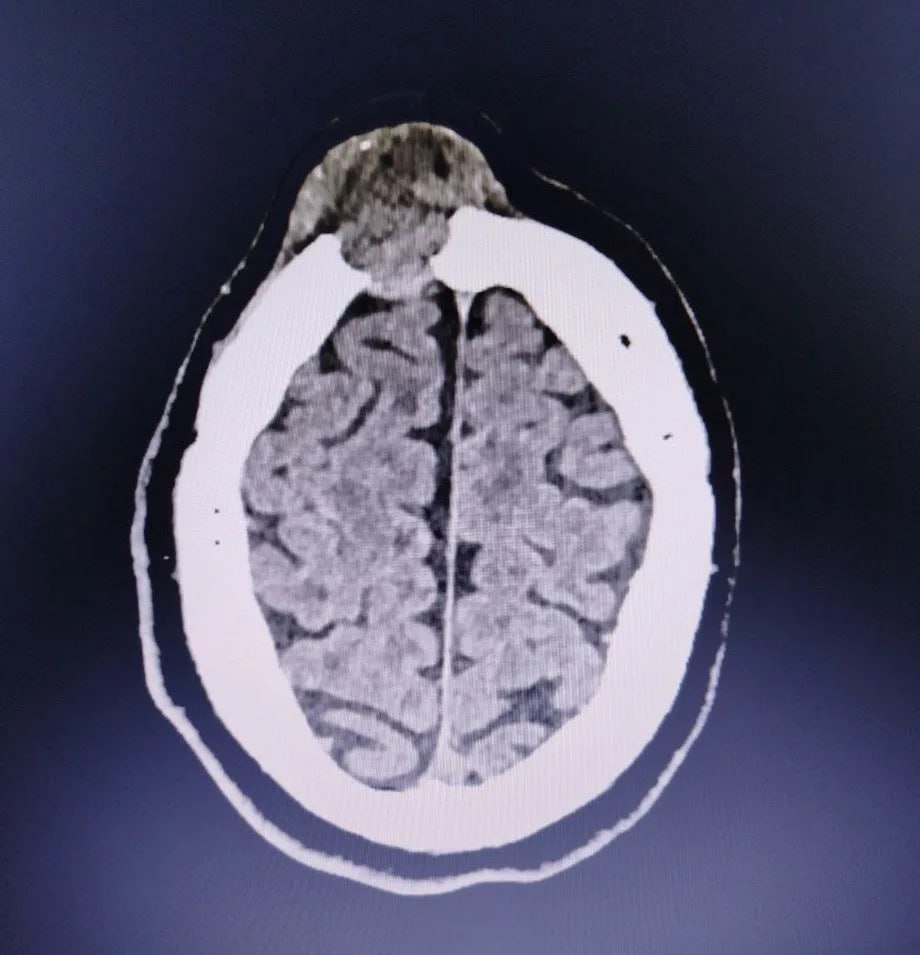

За прошедшее время она не только не прошла, но и немного подросла. Компьютерная томография показала, что это опухоль, которая уже начала разрушать лобную кость.

Случай оказался непростым: один край опухоли лежал над самой крупной веной мозга, а другой разрушал стенки лобных пазух. В результате образование создало сообщение между полостью черепа, полостью носа и внешней средой, а это опасно развитием гнойных осложнений.